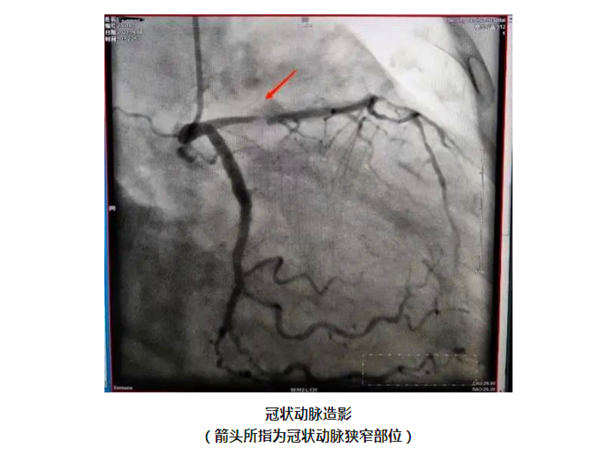

检查的结果可谓亦喜亦忧。喜的是:造成阚阿姨心肌梗死的血栓自己已溶解了,血管并没有完全堵死,这种情况在心肌梗死的患者中出现的可能性不到十分之一。忧的是:阚阿姨心脏上的三根血管都存在严重的病变,其中导致这次心肌梗死的左冠状动脉前降支狭窄到达了95%,并且伴有严重的钙化。